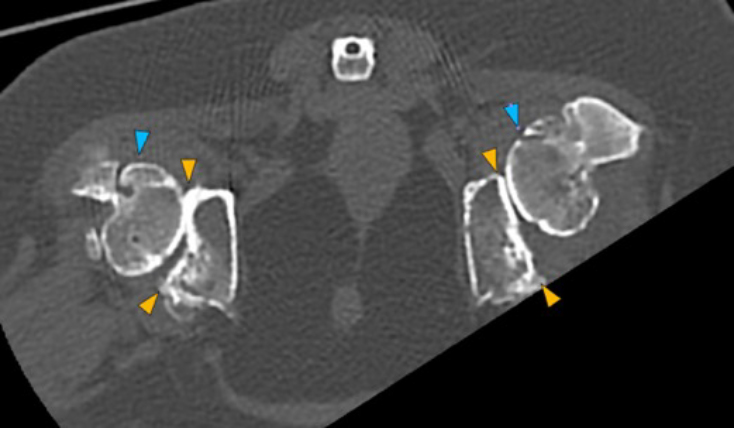

In both coxofemoral joints partially included, there is severe flattening of both acetabula (orange arrows), with marked incongruity of the joint, with dorsal displacement (subluxation) of both femoral heads (blue arrows). In addition, there is severe periarticular new bone formation affecting both acetabula, femoral heads and necks.

• Changes in both coxofemoral joints consistent with severe degenerative coxofemoral joint disease associated with bilateral hip dysplasia.